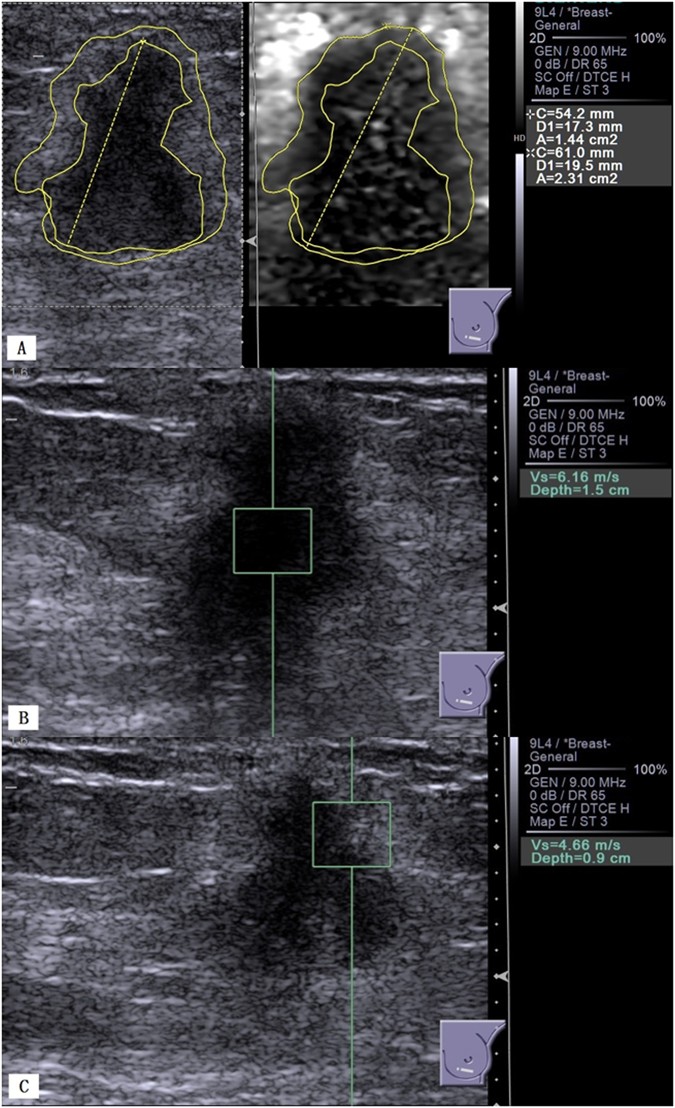

Invasive ductal carcinoma of the left breast in a 50-year-old woman. (A), B-mode US shows a 19.6 mm hypoechoic solid lesion with irregular margins (left); VTI shows a dark lesion with an AR = 1.60 (2.31/1.44) (right). (B) VTQ measures an SWV of 6.16 m/s in the lesion. (C) VTQ measures an SWV of 4.66 m/s in the boundary zone of the lesion.

The mean AR of the malignant lesions was significantly larger than that of the benign lesions (1.34 ± 0.23 vs. 0.99 ± 0.18, P < 0.001; Figs 1 and 2). ROC curve analysis for the differentiation between benign and malignant lesions gave a cutoff AR value of 1.17, and this cutoff point yielded a sensitivity of 91.2% (52/57), specificity of 85.9% (55/57), accuracy of 88.4% (107/121), PPV of 85.2% (52/61), NPV of 91.7% (55/60), false-positive rate of 14.1% (9/64), and false-negative rate of 8.8% (5/57). The AUC was 0.921 (95% CI: 0.889, 0.974).

The malignant group showed significantly higher SWVi (4.06 ± 1.62 m/s vs. 2.15 ± 0.63 m/s), SWVb (3.42 ± 1.67 m/s vs. 1.85 ± 0.61 m/s), and SWVrat (4.33 ± 1.88 vs. 2.37 ± 0.80)values than did the benign group (all P < 0.001, Table 3). The diagnostic performance of the SWV quantitative parametershas been summarized in Table 4. An optimal SWVi cutoff of 3.09 m/s yielded a sensitivity of 68.4% (39/57), specificity of 93.7% (60/64), accuracy of 81.8% (99/121), PPV of 90.7% (39/43), NPV of 16.9% (60/78), false-positive rate of 6.3% (4/64), and false-negative rate of 25% (14/57). It was associated with the highest AUC value among all SWV parameters (0.851, 95% CI: 0.775, 0.909), but did not significantly differ from other SWV parameters (all P > 0.05).